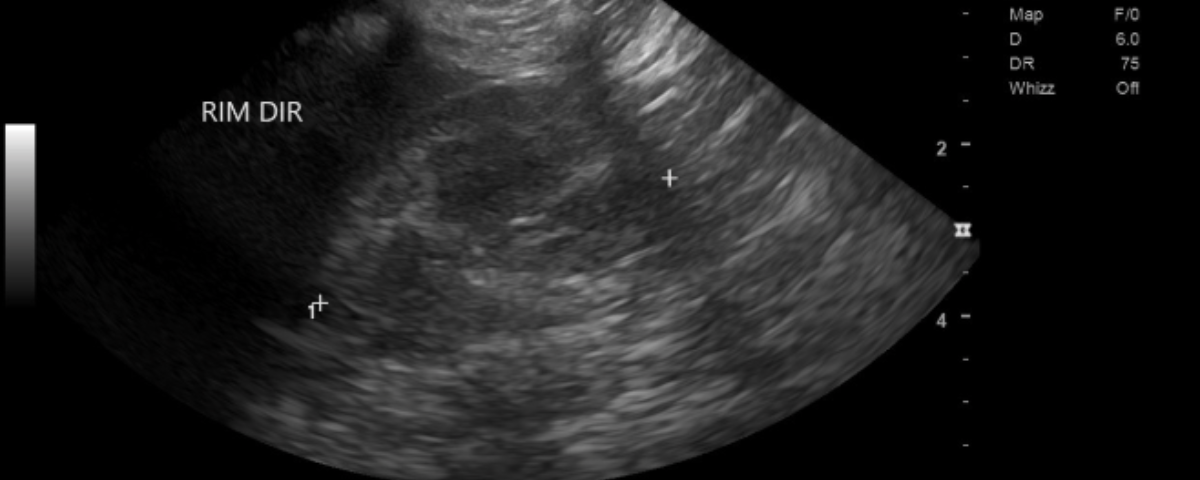

Ultrassonografia abdominal – rins

Ambos os rins apresentam dimensões preservadas, com discreta indefinição dos limites corticomedulares e pequenos pontos de mineralização em recessos pélvicos. Como a função renal está preservada, com adequada capacidade de concentração urinária e bioquímica normal, esses achados serão apenas acompanhados anualmente.